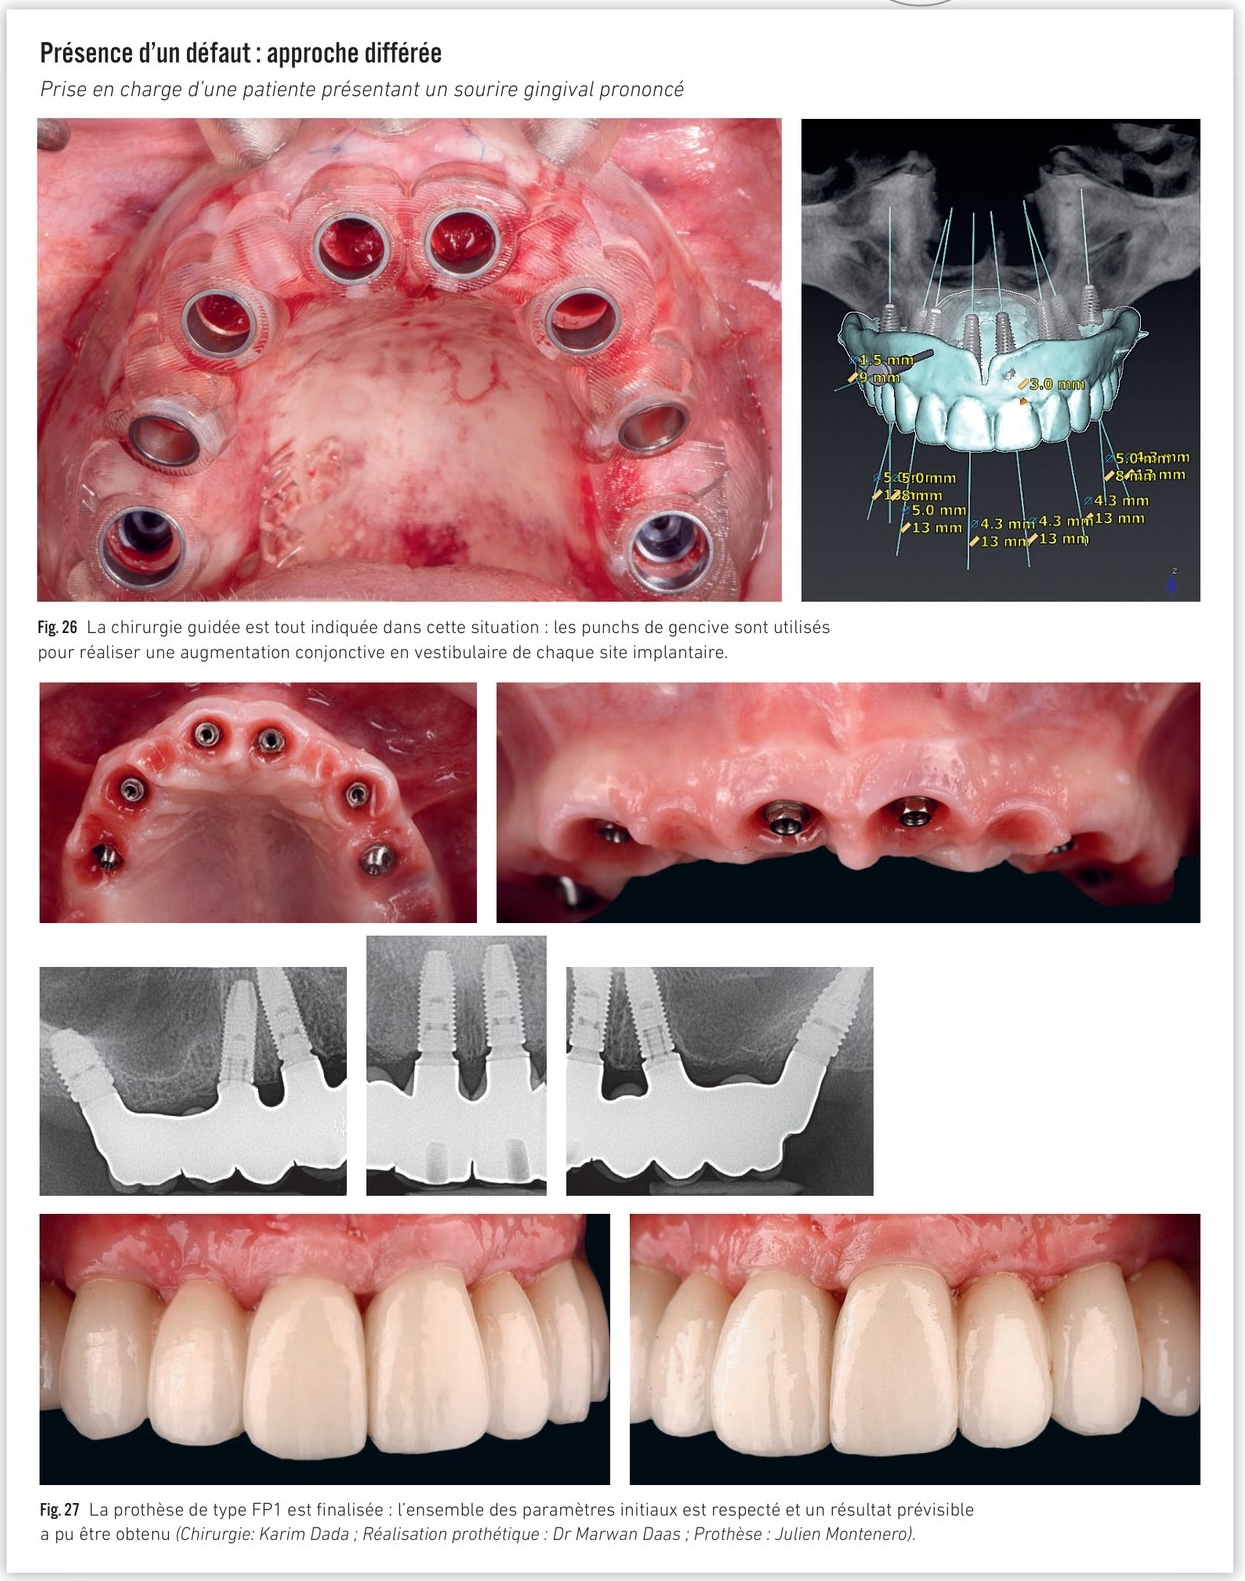

Présence d'un défaut — approche différée

Prise en charge d'une patiente présentant un sourire gingival prononcé avec indication d'ostéotomie de réduction. La chirurgie guidée est tout indiquée dans cette situation : les punchs de gencive sont utilisés pour réaliser une augmentation conjonctive en vestibulaire de chaque site implantaire.

Cas clinique — patiente avec sourire gingival prononcé, chirurgie guidée et résultat FP1